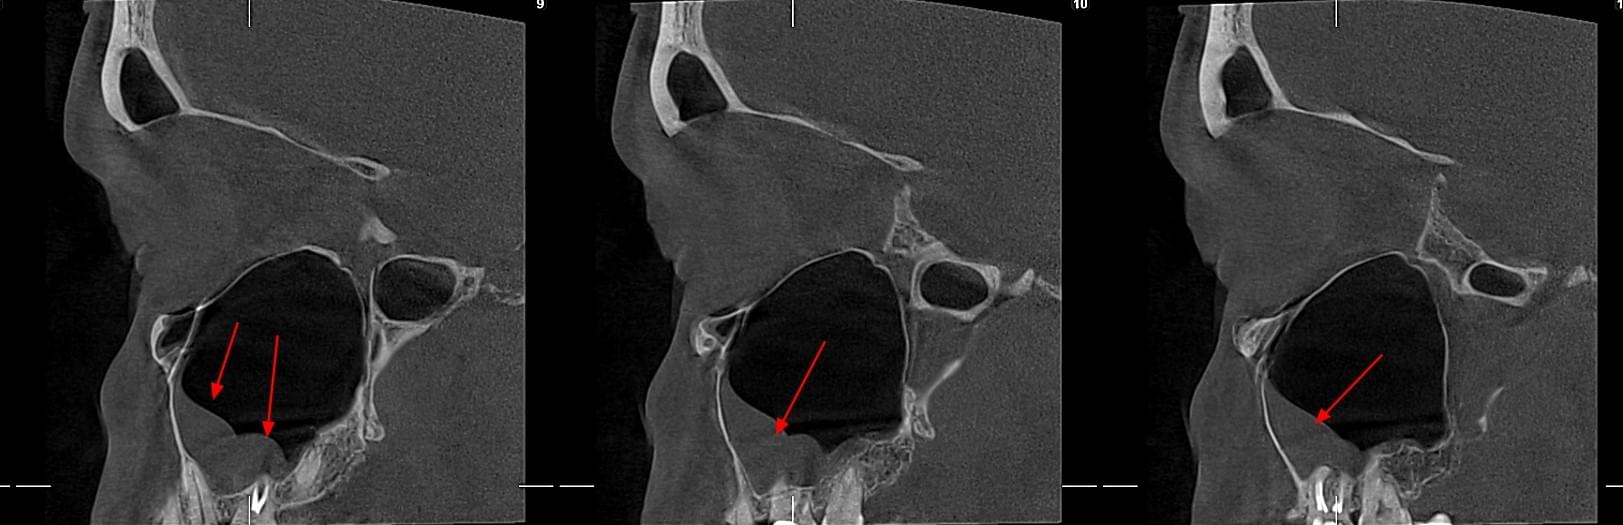

КПКТ (конусно-променева комп’ютерна томографія) — це 3D-знімок високої роздільної здатності. На відміну від звичайного рентгену, КТ показує:

Діагностика гайморових пазух за допомогою КТ